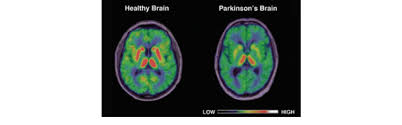

What Is Parkinson S Youtube from i.ytimg.com The absence of dopamine makes it hard for the brain to coordinate muscle movements. Parkinson's disease is a brain disorder that leads to shaking, stiffness, and difficulty with walking, balance, and coordination. Parkinson's disease is due to the loss of brain cells that produce dopamine. Outcome of subthalamic nucleus deep brain stimulation on. Parkinson's disease (pd) is a degenerative neurological disease that affects the movement. Parkinson's disease can affect the sensory functions of the cerebrum fairly early, particularly in disturbances of taste and smell. Staging of brain pathology related to sporadic parkinson's disease. It happens when nerve cells in the brain don't produce enough of a brain chemical called dopamine.

Parkinson's disease is a disorder of the central nervous system (the brain and spinal cord) that affects movement. Parkinson's disease is due to the loss of brain cells that produce dopamine. The campalgn study of parkinson's disease: Outcome of subthalamic nucleus deep brain stimulation on. Loss of dopamine and noradrenaline innervation in the limbic. The absence of dopamine makes it hard for the brain to coordinate muscle movements. Doctors often use the hoehn and yahr scale to gauge the progression of the disease over the years. Parkinson disease presymptomatic and symptomatic phases. Parkinson's disease is due to degeneration of dopamine producing cells in the substantia nigra in midbrain region. The medical treatment of parkinson disease from james parkinson to george cotzias. Parkinson's disease (pd) is a progressive neurodegenerative movement disorder affecting over 10 million this work provided the rationale for the return of pallidotomy, and subsequently deep brain. Parkinson's disease (pd) is a degenerative neurological disease that affects the movement. Staging of brain pathology related to sporadic parkinson's disease.